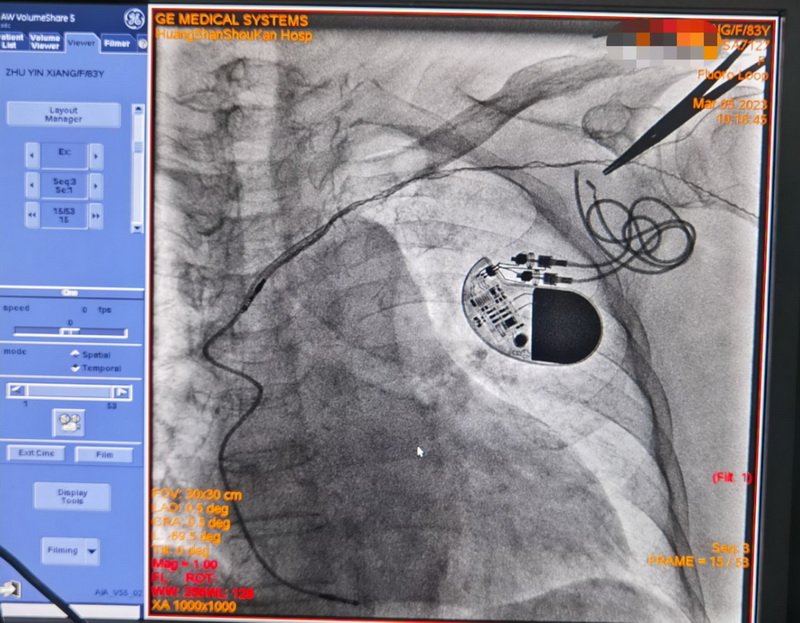

3月5日,外院专家与心内科团队历经2小时,按照预定的方案顺利拔除了起搏导线,攻克了整个医疗过程中最为困难的一步。

术后朱奶奶情况一直很稳定。经讨论后,为避免类似的问题再次发生,吴捷华主任决定为朱奶奶植入无导线起搏器。相较于传统心脏起搏器,无导线起搏器体积缩小了90%,且弥补了传统起搏器电极导线需要导线进行脉冲的缺点,将脉冲发生器和电极合为一体,未来不会产生囊袋破损感染的风险。

半个多月后,随着双腔无导线起搏器成功植入在朱奶奶体内,囊袋感染的第二次心脏危机被彻底解除。朱奶奶的心脏又继续忠诚地履行起它的职责,继续有规律地跳动。